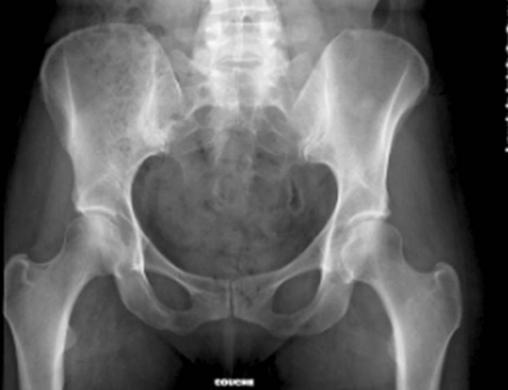

Radiographie du bassin

Radiographie normale du bassin.